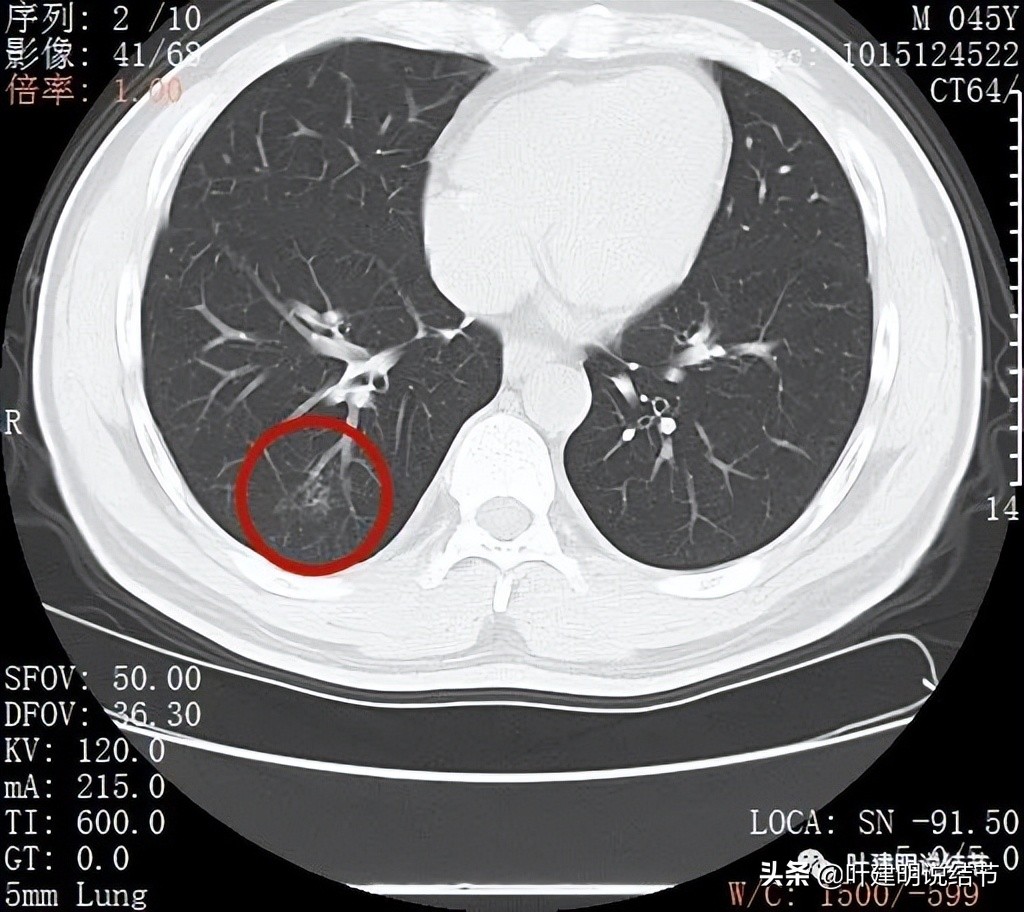

再来看薄层扫描:

病灶感觉很散在,但内部有扩张的细支气管(黄色箭头)、边缘略显不清(绿色箭头),部分有偏实性(粉色箭头)。